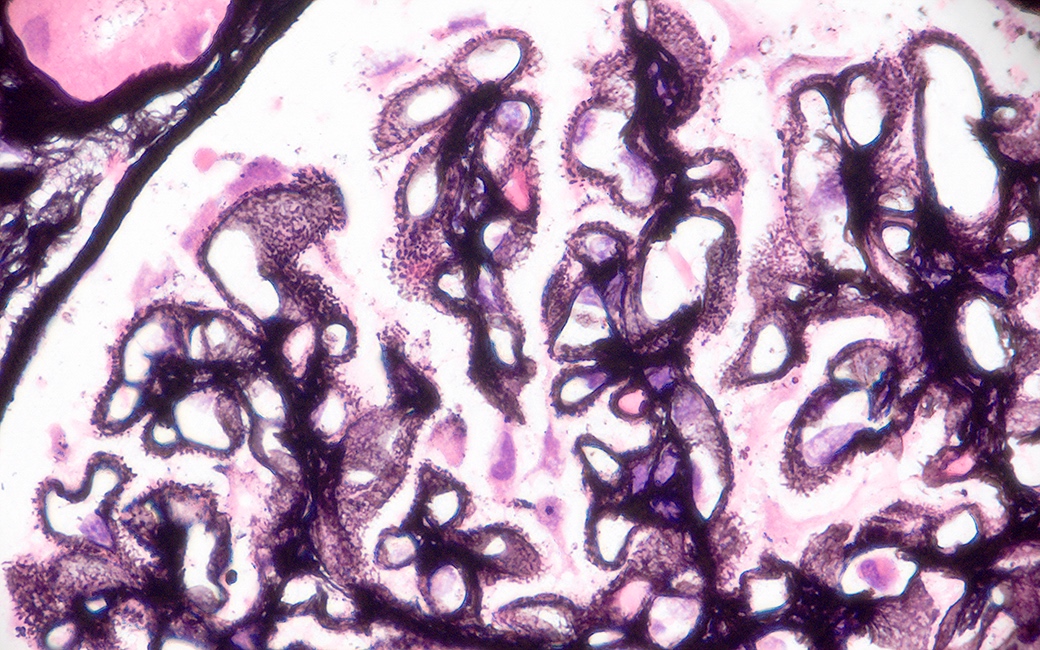

Microscopic (histologic) images

Contributed by Alexei Mikhailov, M.D., Ph.D.

- PAS special stain is the most useful staining method in every LN class to evaluate mesangial and endocapillary changes

- Masson trichrome special stain is most useful in LN classes III and IV and helps to detect foci of fibrinoid necrosis, glomerular and interstitial sclerosing changes

- PAMS (Jones Silver) special stain is most useful in LN class V and emphasizes capillary wall thickening and neomembrane formation (microspikes and domes)